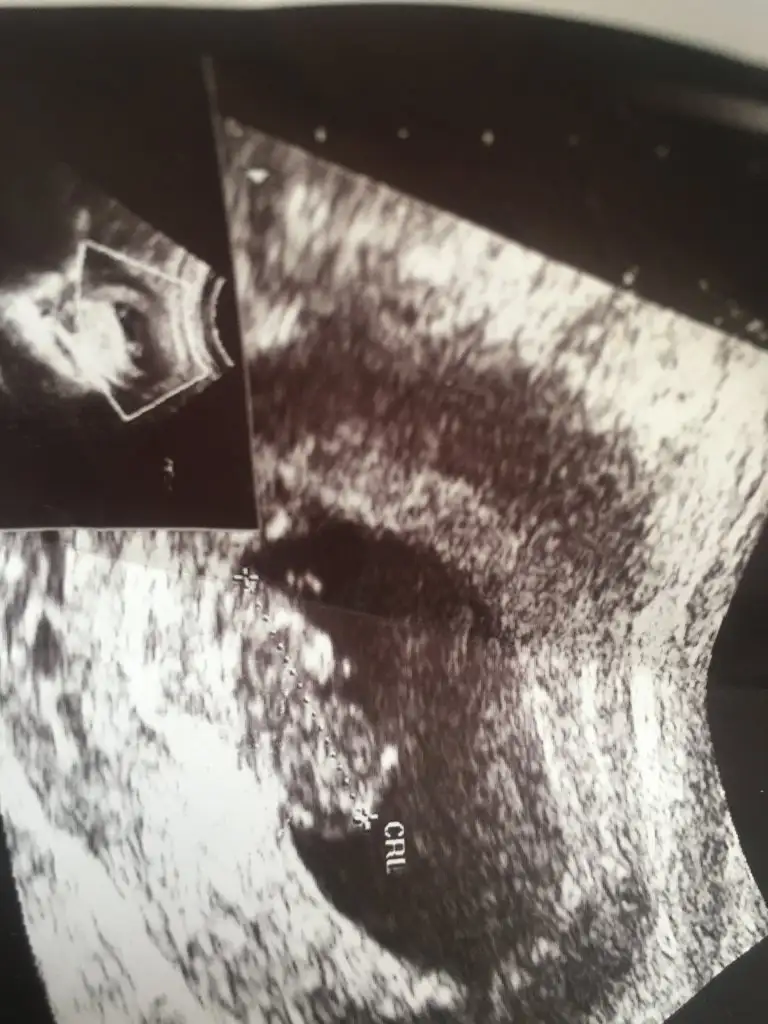

dr soylemeden siz gorun genital nub teorisi ( bebegin cinsiyeti)

Bunlarda bir arkadaşımın 😊 tahmin yürütülmüsğn 😂🙏 lütfen çok merak editör yazık

Tatlım ben sadece kese göre tahmin ettim 🙈 birde 11+4 göre kız gibi ama sen 13 hafta olursa paylaşın daha net nub tahmini için